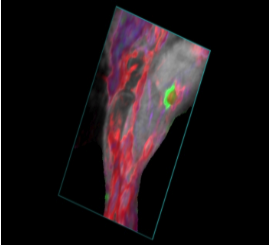

フォトアコースティックによる機能的情報は、超音波のB-Mode画像上に統合・オーバーレイ表示できる為、解剖学的位置情報と共に解釈する事が可能です。

- 生体内深部組織(2-3cm)において、無侵襲・リアルタイムイメージングを実現

- 酸素飽和度・総ヘモグロビン量の算出(解剖学的B モード画像との統合表示、0.5Hz)

- 色素ラベリングによる特定細胞・分子の検出